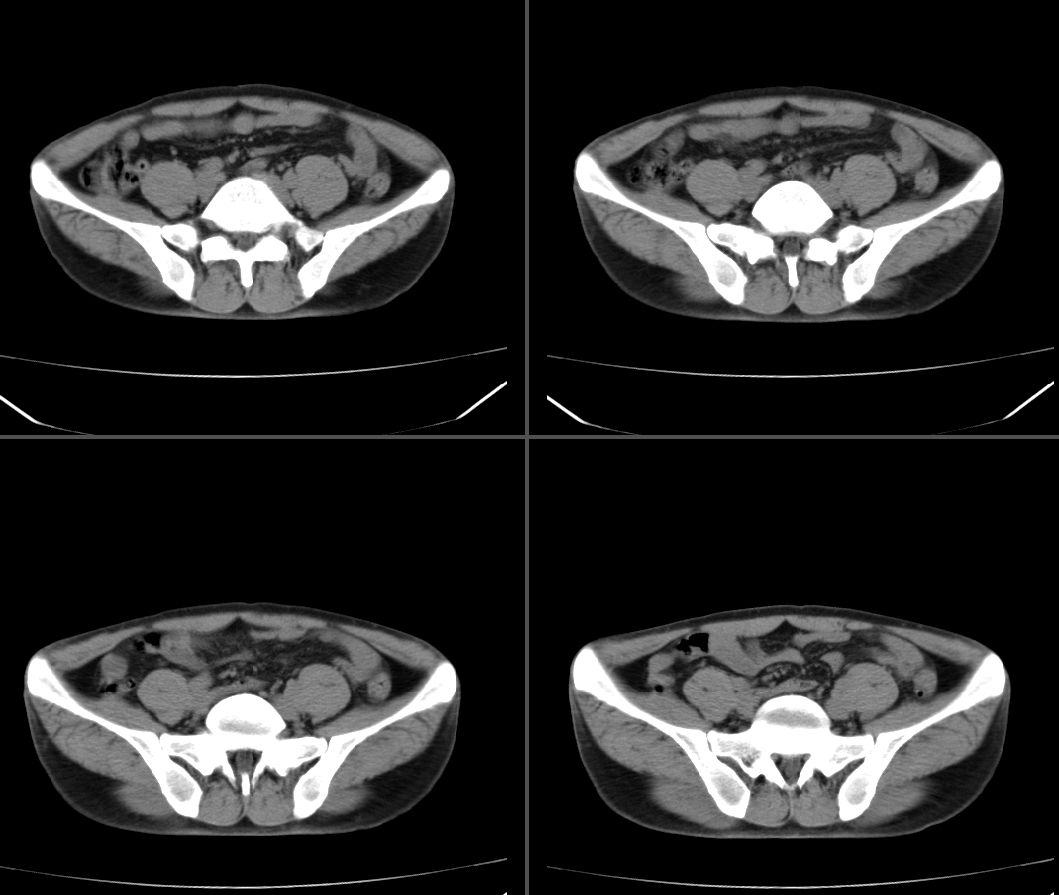

标题: CT23964:45岁,男性,发现右下腹包块半年,余病史不详,请 [打印本页]

标题: CT23964:45岁,男性,发现右下腹包块半年,余病史不详,请

定位:右腹直肌鞘下部

病灶特点:分界清,边缘光整,囊性密度,病灶成长椭圆形,病灶处腹直肌受压萎缩,病灶与膀胱处有相似密度管状灶(该征象因肠道未作准备,不能确切)

拟诊:1.淋巴管囊肿

2.神经纤维鞘瘤

3.脐尿管囊肿

建议:1.磁共振扫描,2.肠道准备后,增强扫描,3.穿刺活检